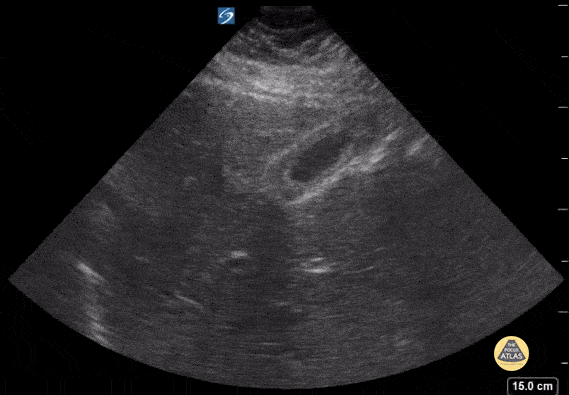

16 y/o F with RUQ pain. POCUS shows a thickened gallbladder wall. In the appropriate setting this could be consistent with cholecystitis though thickening of the gallbladder wall can also be a normal finding following eating a meal. Contributor: Kathryn Pade, MD, Rady Children's Hospital San Diego